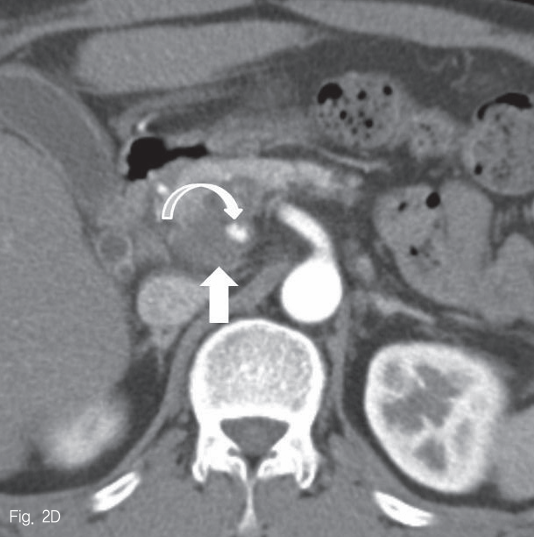

Contrast-enhanced MRI (C) and CT (D) images reveal well-enhancing nodular lesion (curved arrows) in medial aspect of the pancreatic mass (arrow).

Fig 2D

초음파 검사에서 췌장 두부에 약 2.5cm 크기의 종괴가 있었다 (Fig. 1). 췌장 자기공명영상에서 종괴는 T1-weighted image에서 다양한 신호강도를 보였고, T2-weighted image 에서는 저신호강도를 보여 다양한 단계의 출혈을 포함한 병변으로 생각하였다 (Fig. 2A-B). 조영 증강 자기공명영상 및 조영 증강 복부 전산화단층촬영에서 종괴의 내측으로 혈관과 비슷한 조영 증강을 보이는 1cm 크기의 병변이 보여 가성동맥류로 진단하였다 (Fig. 2C-D).